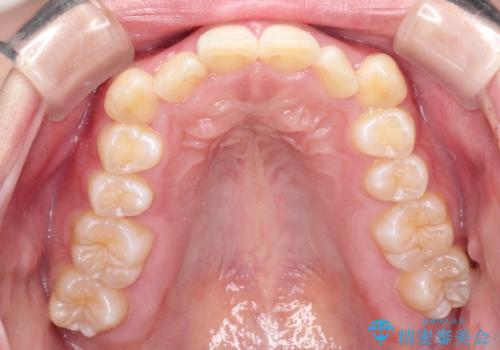

- 前歯の凸凹と深い噛み合わせを主訴に来院されました。

下の前歯が見えないほどのディープバイト症例でした。

ワイヤー矯正にて下顎前歯の圧下と臼歯部の挺出を効率的に行うことができました。